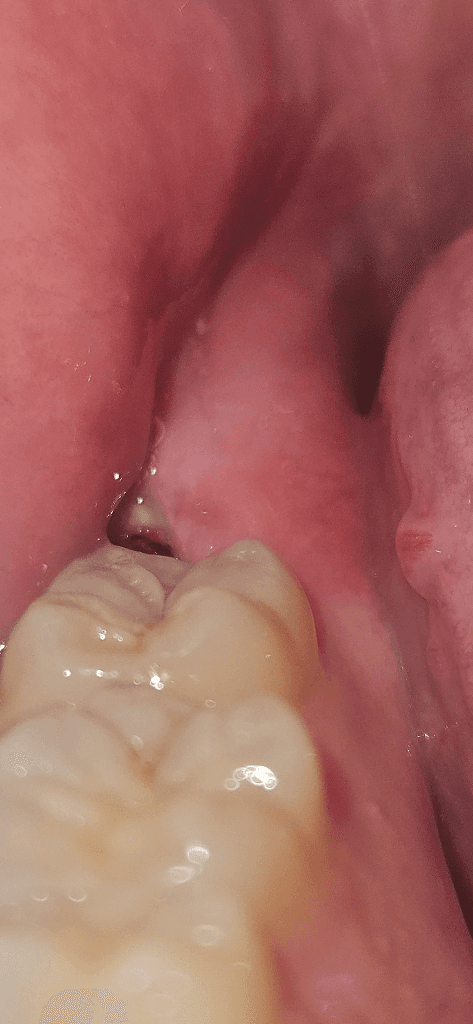

부분 맹출된 사랑니에 음식물이 자주 끼고 구강위생관리가 되지 않아 충치가 생긴 것으로 보입니다. 가끔 통증을 일으키는 것은 사랑니 치아머리 주위의 잇몸에서 염증이 발생하는 치관주위염 때문일 수 있습니다. 치과에서 검진받으시고 사랑니 발치하는 것을 권유드립니다.

사랑니가 잇는부분에 사랑니가 일부분만 노출되서 그부위에 음식물이 꼇거나 염증이 생겻을 가능성이 높아 보입니다.

방사선 사진상 사랑니가 충치가 생긴 것 같지는 않으나 해당 부위 사랑니의 부분 매복으로 인해 잇몸이 벌어져 있고 잇몸도 부어있는 상태입니다.

사진으로 봤을 경우에는 사랑니가 부분적으로 맹출되고 있는 것으로 보입니다. 사랑니가 기울어져 나있을 경우 해당 부위에 이물질이 끼게 되어 주변 조직에 염증이나 충치를 일으켜 발치를 해주는 것이 좋을 수 있습니다.